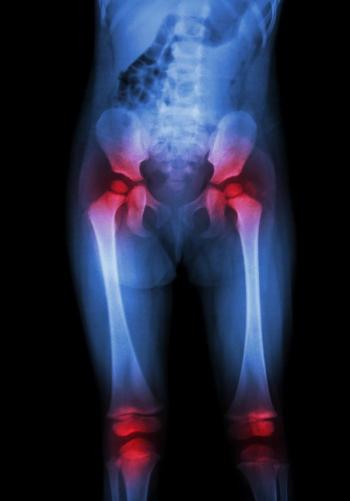

A study of patients undergoing total hip arthroplasty found that patients with psoriatic arthritis face no greater risk of poor outcomes than patients who get hip replacements because of osteoarthritis.

Study shows that patients with psoriatic arthritis and cutaneous psoriasis could be good candidates for total hip replacement.